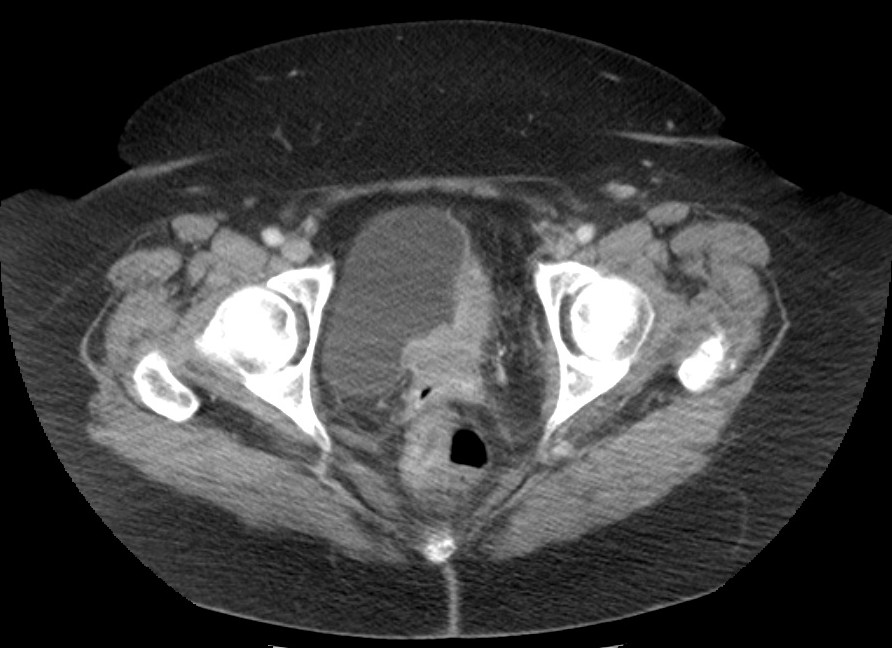

Paciente de 63 años, fumador que presenta hematuria macroscópica desde hace 10 días.

Ante dicho hallazgo se proceden a realizar estudios de imagen complementarios.

Estamos claramente ante un proceso neofromativo que afecta a la vejiga, el cáncer urológico más frecuente.

CARCINOMA VESICAL.